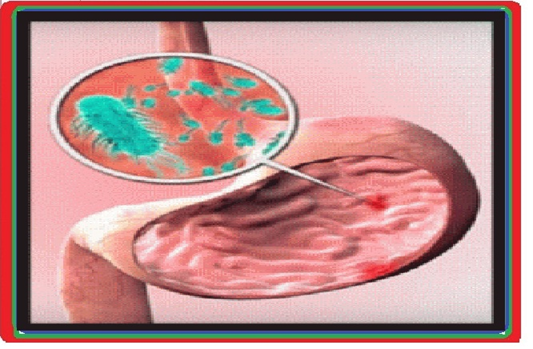

و قرحة المعدة و الاثني عشر بجانب استقصاء جرثومة هيليكوباكتير بلوري (8)

تتوظف مثبطات مضخة البروتون (م م ب) في خفض حمض المعدة عبر احباط مضخات الهيدروجين + بوتاسيوم أ ت ب أزا منذ ولوج سوق الاستهلاك لأؤول عقار م م ب سنة 1987م و و وصفات تلك الأدوية آخذة في التصاعد باستمرار دون تراجع نظرا لجودة فعاليتها بجانب فقابلية تحملها الحسنة من طرف المصابين .و حسب ما صرحت به إدارة الضمان الاجتماعي سنة 2019م فان قرابة 196 مليون مصاب بفرنسا تلقوا العلاج بواسطة م م ب (أي ما يرب عن ¼ سكان فرنسا) مصحوبة بارتفاع يقارب 13 % من الاستهلاك في غضون الخمسة سنوات الأواخر لاحظت شفافية الهيئة العليا للصحة(9)

ضمن المصابين الذين تفوق أعمارهم 65 سنة الذين يتلقون العلاج بواسطة أدوية م م ب حضت نسبة 8 % منهم بفحص التنظير الباطني للمعدة المريء والاثني عشر. يوصي بإنجاز هذا الفحص كلما تم الشك في الإصابة بحالة ا م م . و بالرغم الحالة التي يبدو خلالها التنظير طبيعيا بالنسبة لنصف المصابين الذين يعانون من أعراض ا م م فان التنظير يتيح تأكيد وجود ا م م في حالة تشخيص إصابات المريء و خاصة تشخيص آفات أخرى مثل البطانة المخاطية باريت أو تشخيص ورم . يعتقد اذن انجاز هذا الفحص من الأهمية بمكان. وخلاصة حينما يدور الحديث حول العلاج الطويل المدى لكي لا نتجاهل الإصابات التي تتطلب أخذ الموقف الخاص و الحفاض على المراقبة